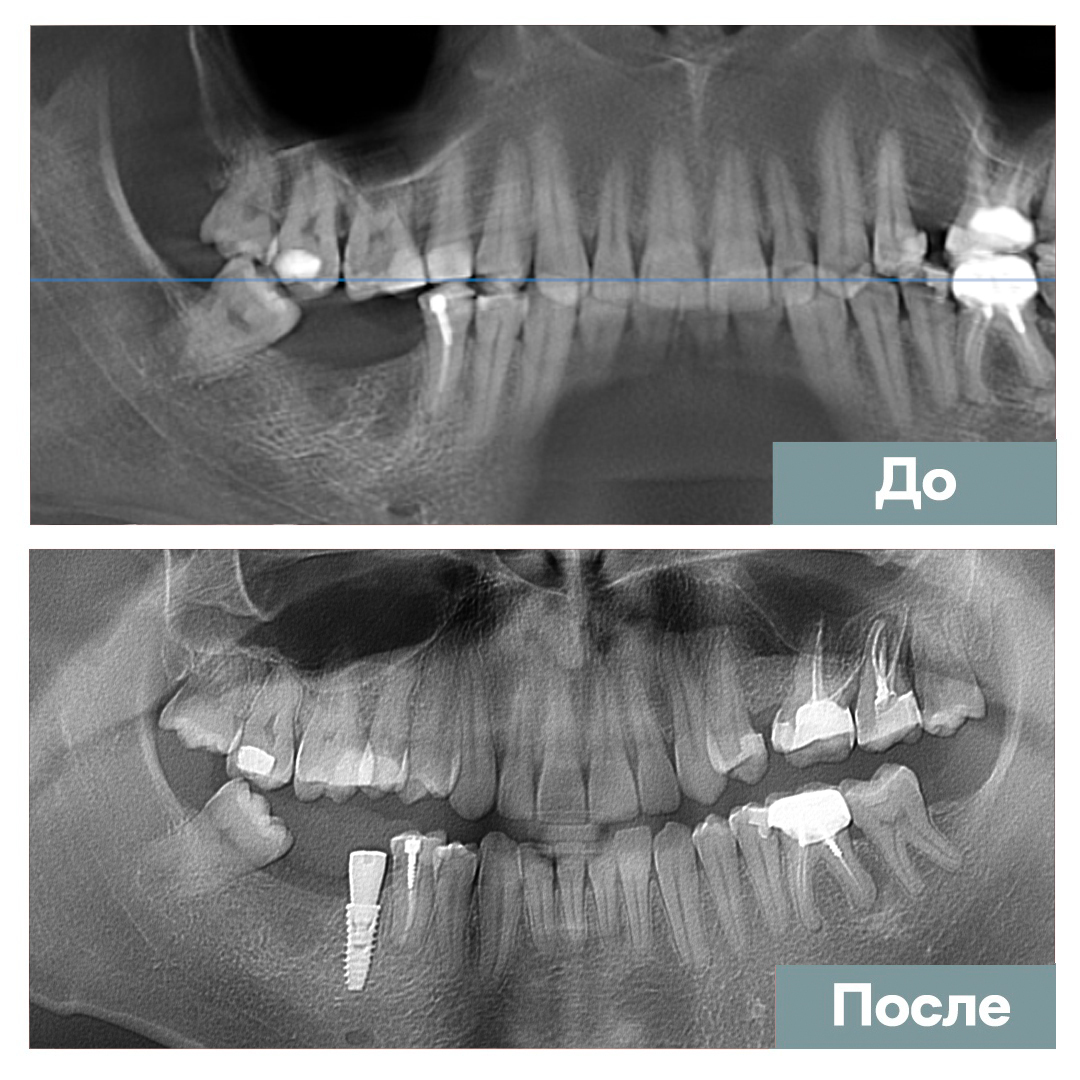

Имплантация 1 ед.

Мазанов